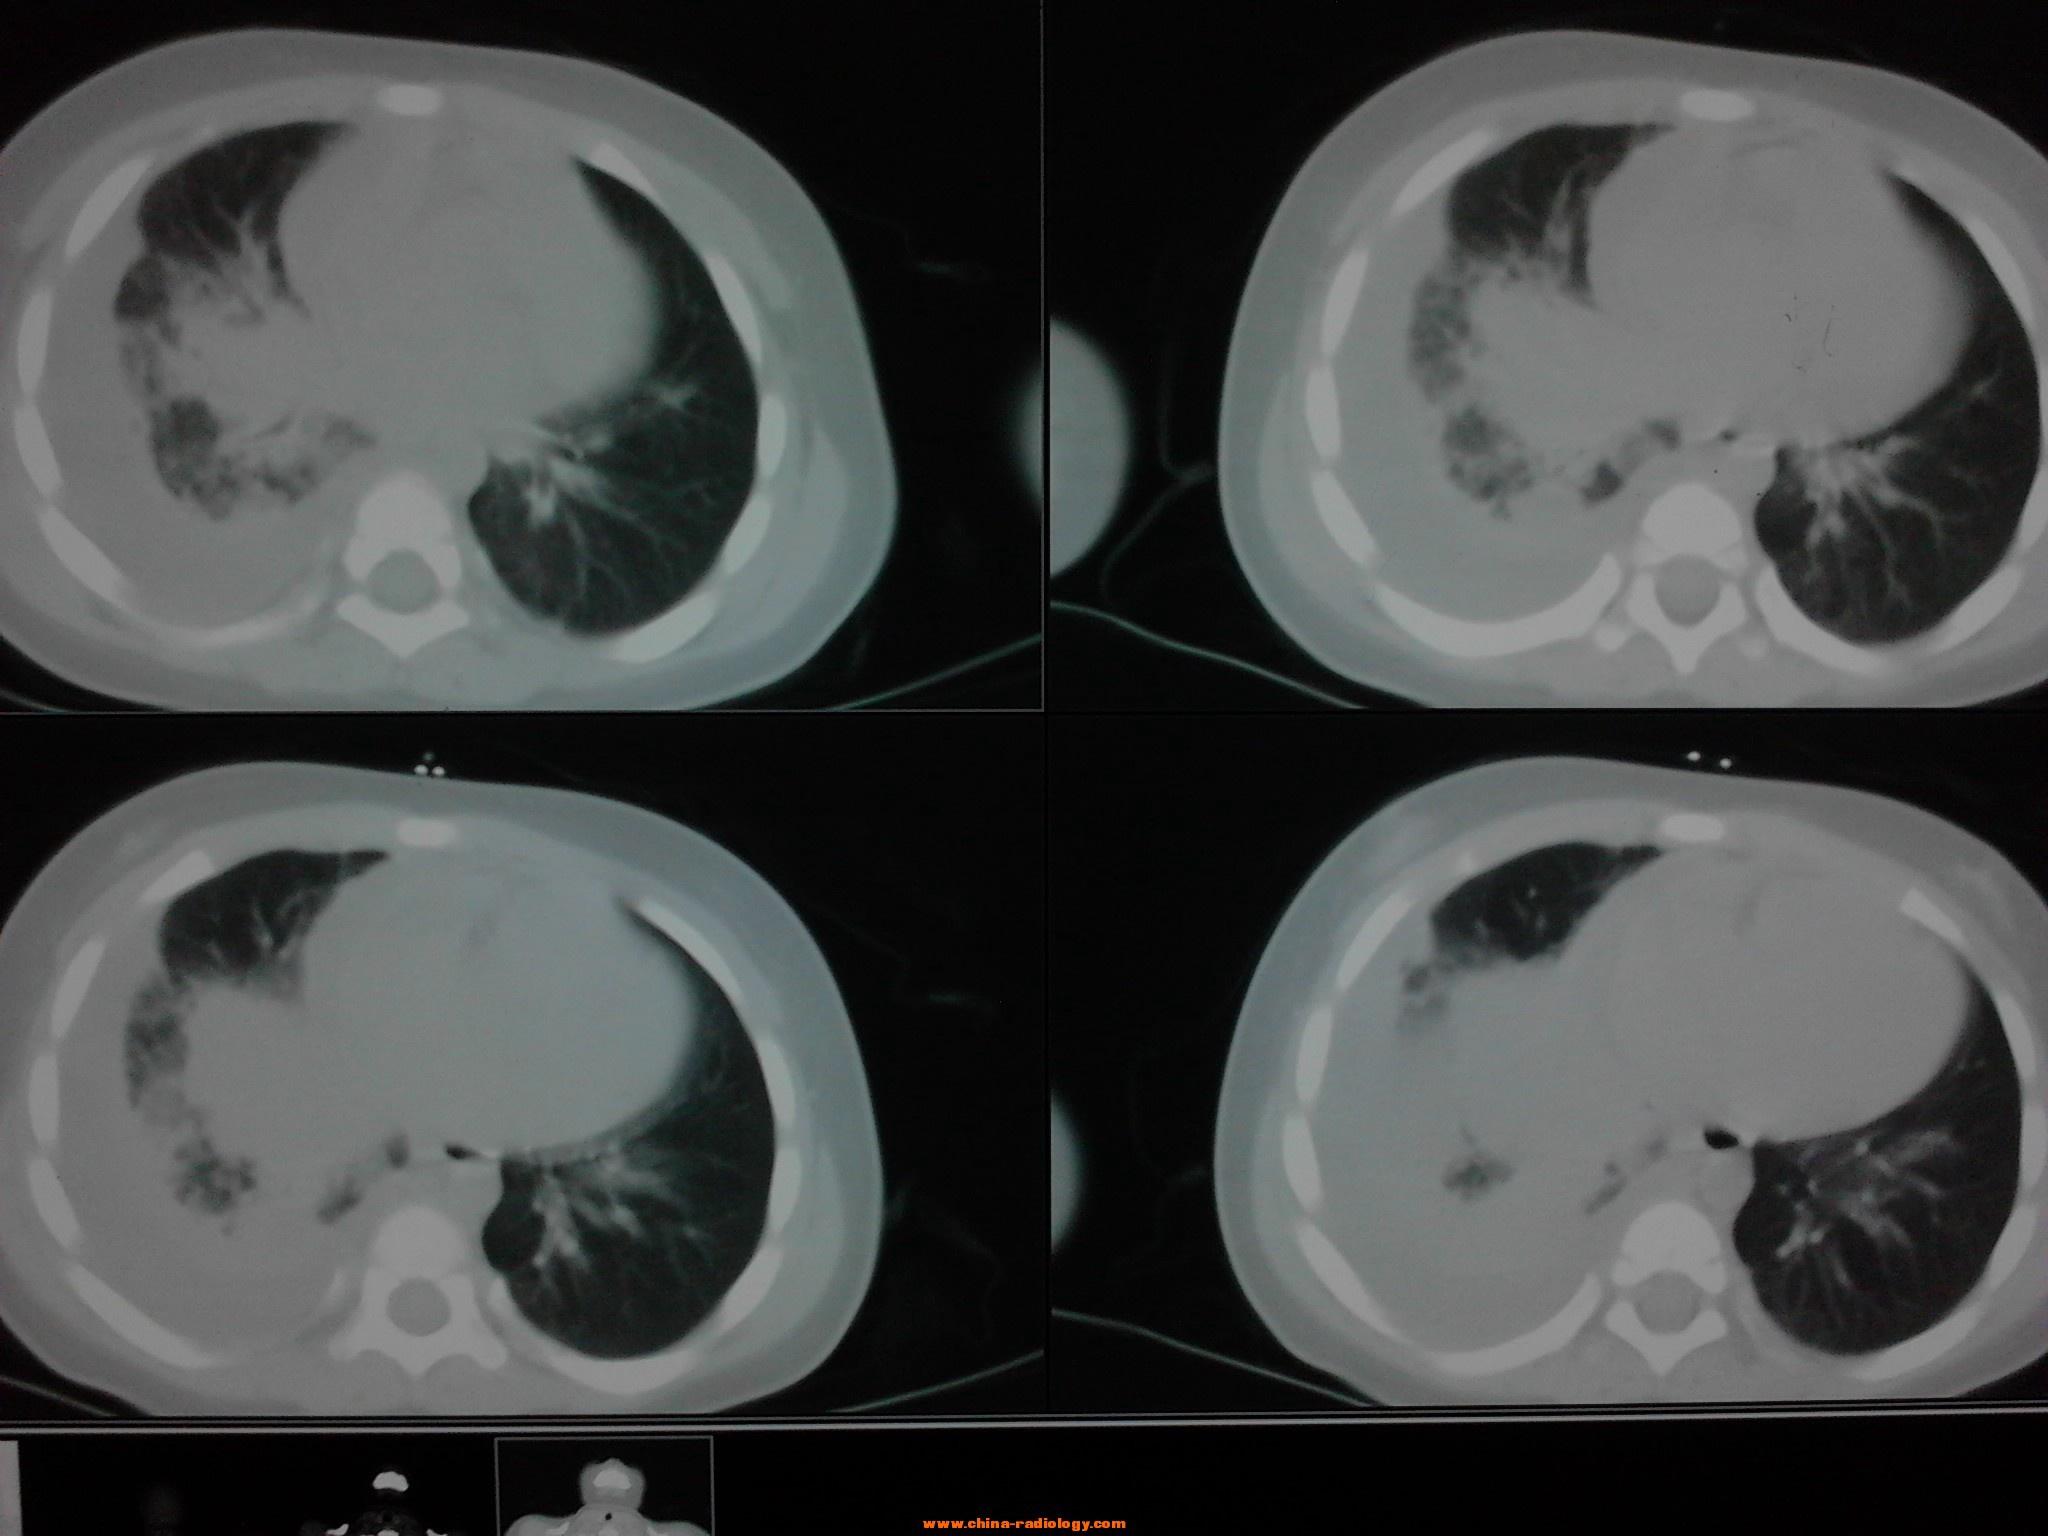

肺纤维化ct表现图片